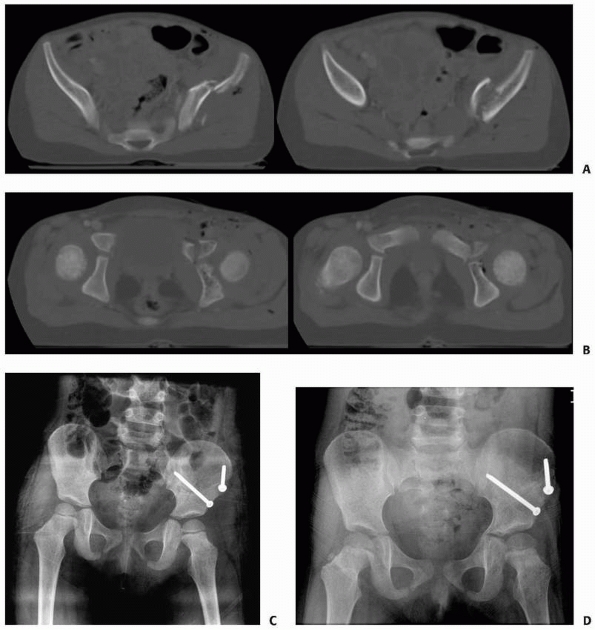

axial, CT scan are indicated to look for anterior ring fracture (Fig. 20-13).

FIGURE 20-13 A 4-year-old with a pelvis fracture primarily with posterior involvement. A. Pelvic outlet radiograph showing a posterior injury at the sacroiliac joint. B. CT scan showing the minimal posterior SI widening. C. CT scan showing no anterior ring injury.